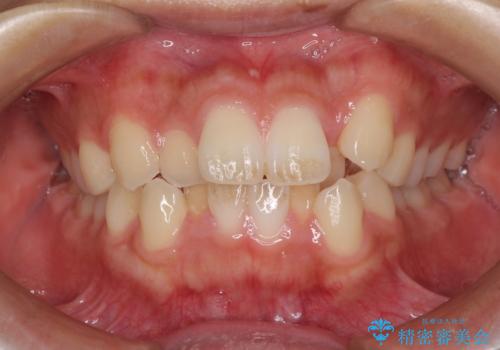

- 前歯のデコボコと口元の突出感を気にして来院された患者様です。

上下左右第一小臼歯4本を抜歯し、ワイヤー装置にて口元を引っ込めるよう矯正治療を行うこととしました。